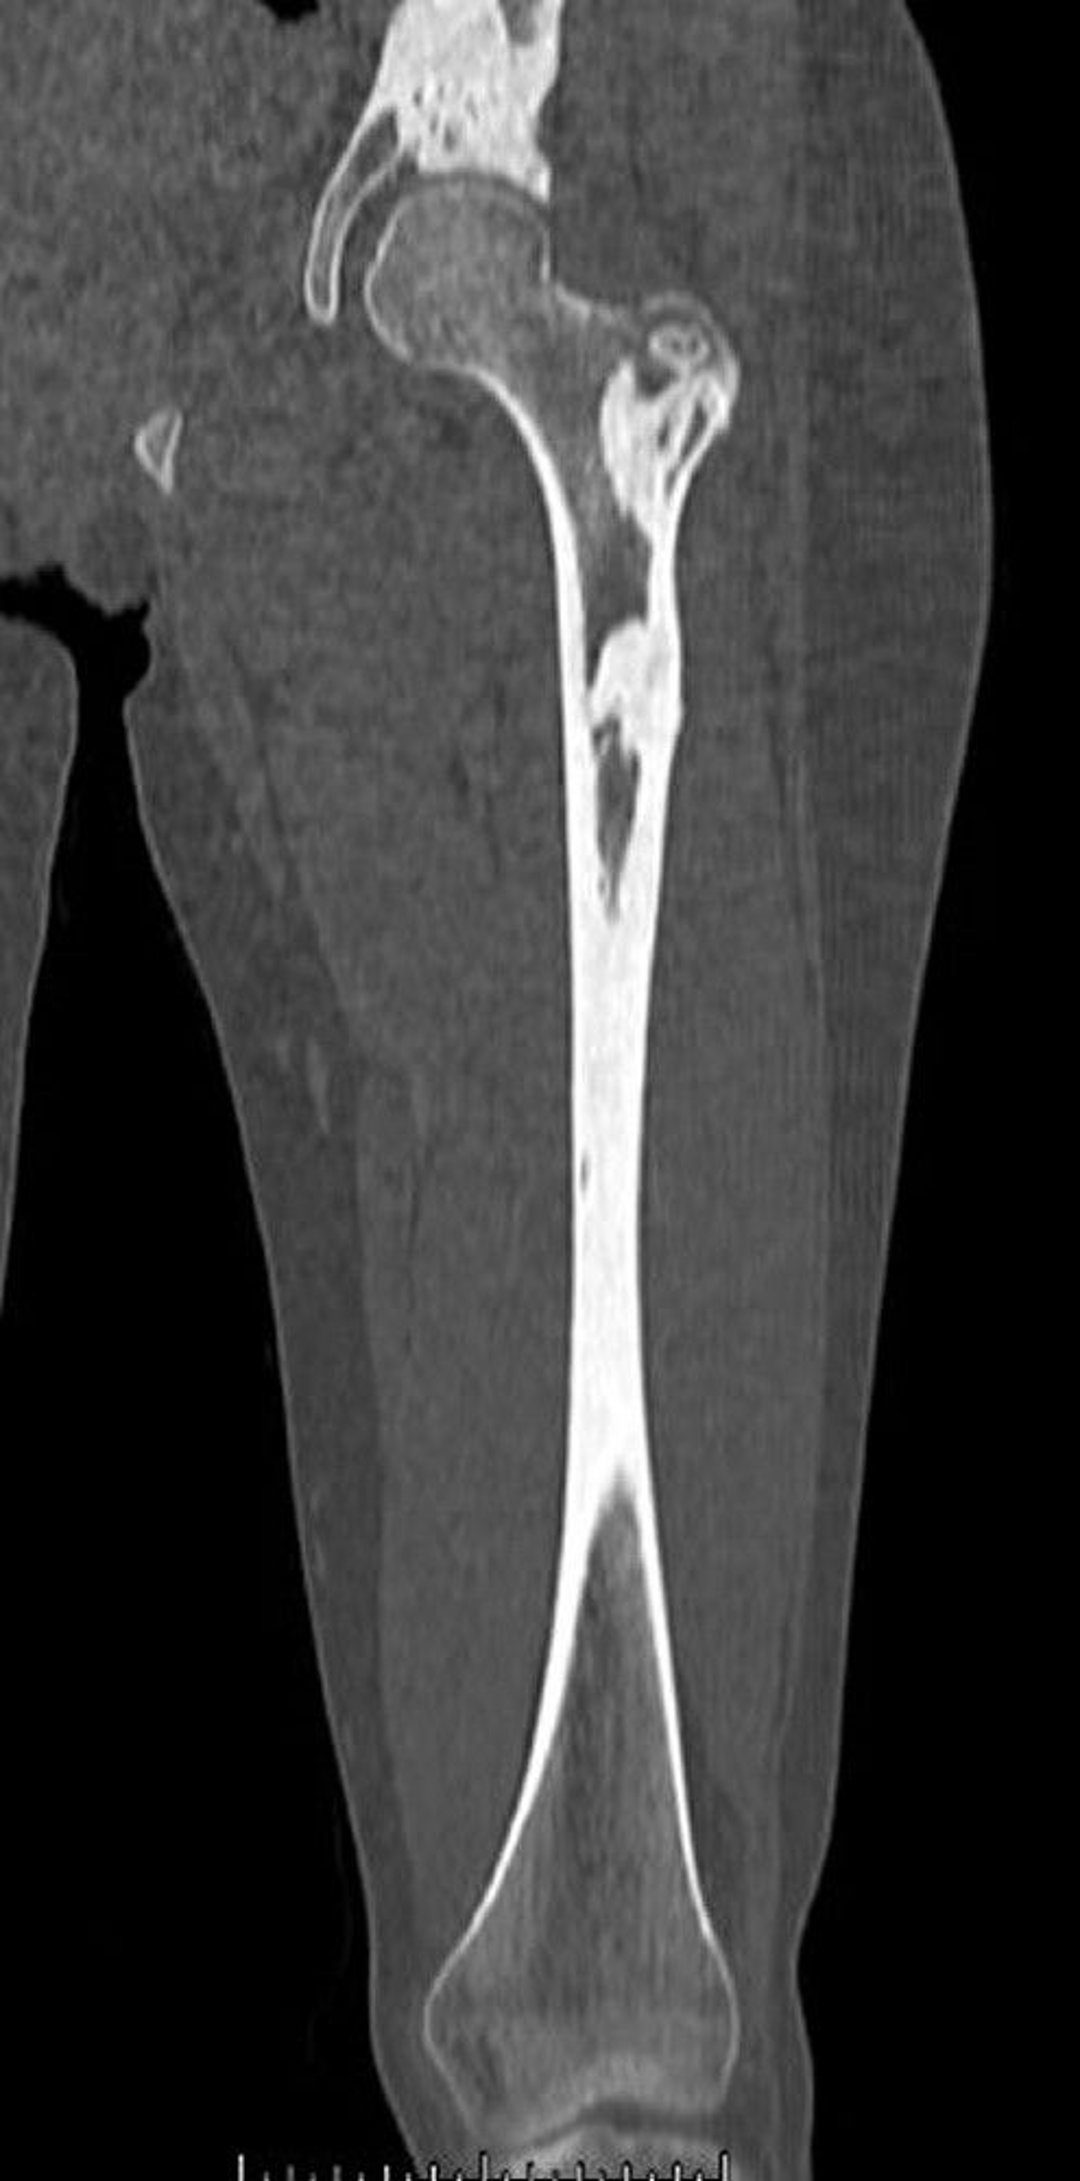

Melorheostosis (CT Scan)

This CT scan shows the dense bone lesions of melorheostosis in the femur and pelvis.

Image courtesy of Michael J. Joyce, MD, and David M. Joyce, MD.